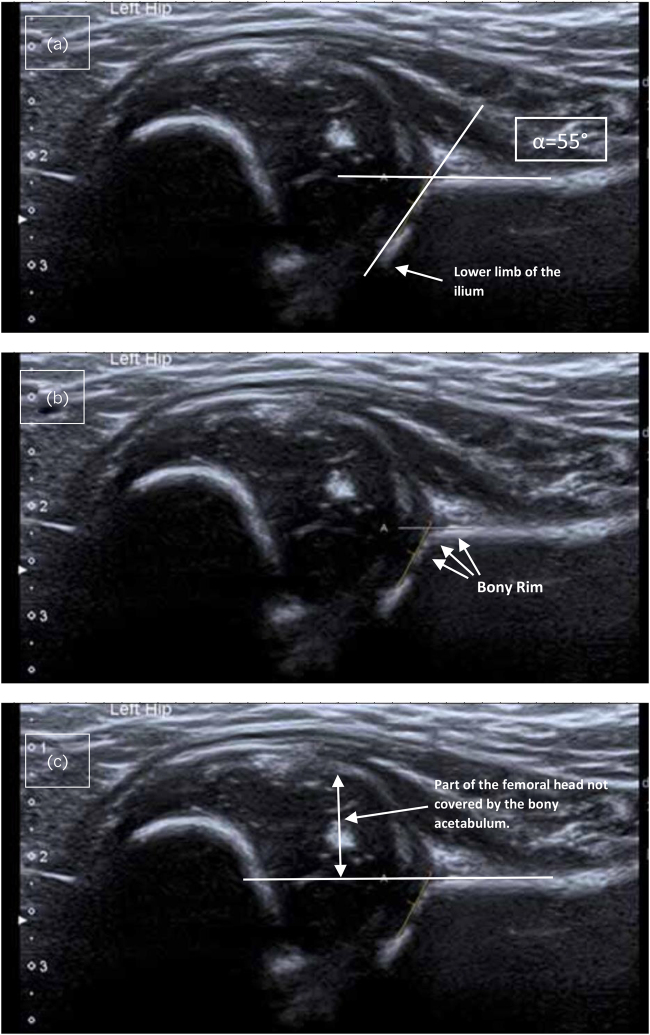

Dislocation of the hip after normal sonographic screening examination: a case report and literature review.